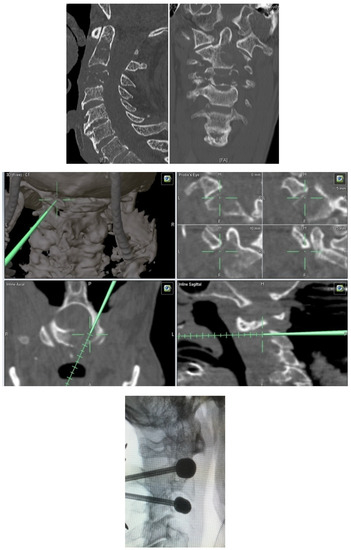

- Unrestricted reconstruction of datasets with views along the path of the needle with planning in 3D and 2D reconstructions (Figure 1).

- Metastatic lesions of C1 are extremely rare, and their treatment by percutaneous cement augmentation is considered to be a technically challenging procedure due to complex anatomy. We also performed percutaneous kyphoplasty in a painful osteolytic lesion located on the left lateral mass of C1 through a posterolateral approach using a 3D CT scan intra-operative navigation system and fluoroscopy (Figure 3) [22].